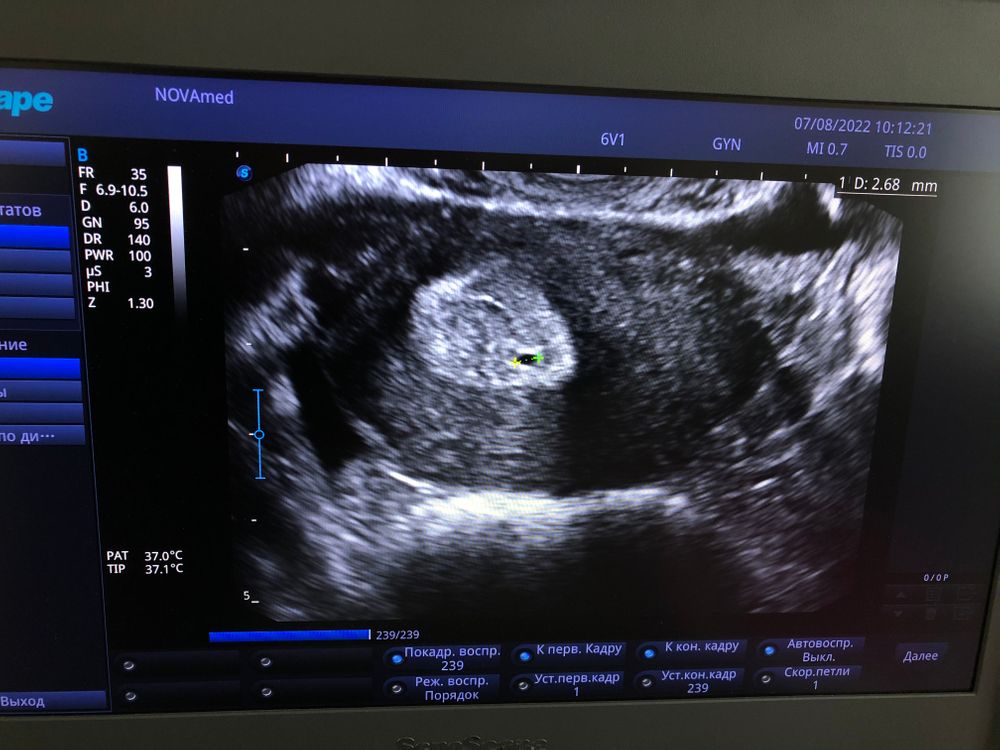

В общем предыстории немного, чтобы было понятно для тех, кто считает в первый раз! Последний цикл был с задержкой большой (у меня последний год не регулярный цикл). В этом цикле сильно была ощутима Овуляция. Поздно начала ее тестить, но полоски были норм! Решила сходить 7.08 на УЗИ, удостовериться была ли овуляция или может вот вот должна быть, а по итогу мне вот такую картину выдают😳👇🏻

На фото якобы что то в матке🙈